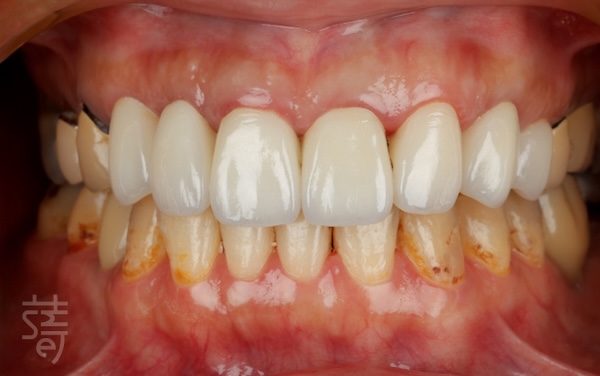

第四階段 全瓷美學,重現自然笑容

Stage Four: All-ceramic artistry — restoring a natural smile

植牙完成後,臨時假牙逐步更換為全瓷牙套。

紀醫師與蒔美數位牙技中心協作,精準微調牙色、形態與笑容曲線。全瓷材質呈現真牙般透明感與光澤,燈光下依舊自然。

每個階段間保留足夠癒合與觀察時間,骨與牙齦穩定生長。最終完成的全瓷牙冠在外觀與功能上達到完美平衡,笑容柔和流暢,自然、自信重現。

After the implants healed, temporary restorations were gradually replaced with custom all-ceramic crowns.

Working closely with the Smile Digital Dental Center, Dr. Chi fine-tuned each detail—from tooth shade to contour and smile line. The all-ceramic material reflected light like natural enamel, giving the teeth a lifelike translucency under any lighting.

Each stage allowed ample time for healing and adjustment, ensuring the bone and gums integrated stably. The final result achieved a seamless harmony between aesthetics and function—a soft, confident smile that felt entirely her own.

久違了!全口植牙重建讓笑容與生活回歸

A Long-Awaited Return: Full-Mouth Reconstruction Restores Smile and Life

重建前,陳太太吃東西總覺得不舒服,笑起來也好尷尬。聚餐時,她不自覺縮小笑容,生怕牙齒鬆動或咬不斷食物。

In the past, Mrs. Chen struggled to eat comfortably, and her smile felt awkward. At gatherings, she would hold back, worried her teeth might feel loose or fail to bite through food.

如今,完整的全口植牙重建讓她能大口咀嚼喜愛食物,也能毫不顧忌地開懷大笑。「現在感覺就像自己的牙齒,非常自在。」她笑著分享。

Now, with full-mouth implants, she can enjoy her favorite foods and laugh freely. “It feels just like my own teeth—so natural,” she shares.

從舒眠治療、導航植牙、即拔即植,到全瓷美學修復,每一步都由醫師團隊細心規劃。這不只是牙齒的重建,更是生活品質的回歸:重新擁有自信笑容、自在進食,找回健康與從容日常。

From sedation and guided implant placement to immediate implants and full-ceramic restoration, every step was carefully planned. This reconstruction isn’t just about teeth—it’s a return to quality of life: confident smiles, comfortable eating, and reclaiming her sense of ease and well-being.